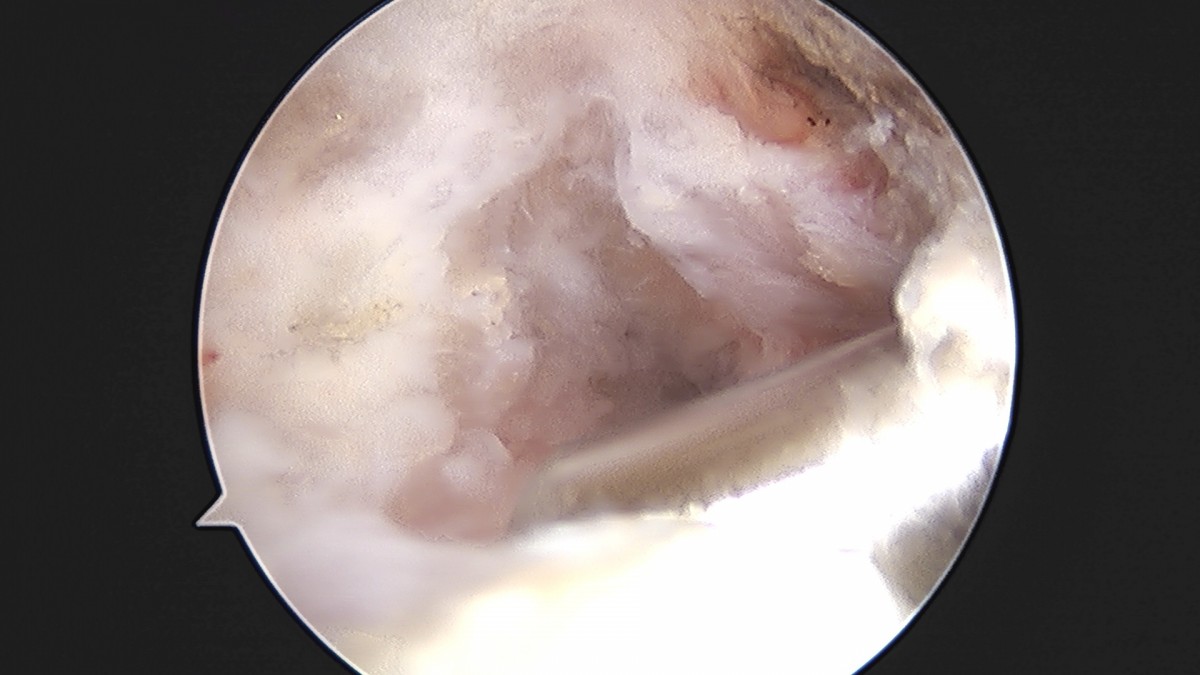

이재상원장님 어깨 견봉하 감압술 이승O 환자

작성자 최고관리자 댓글 0건 조회 806회 작성일 25-09-16 15:26